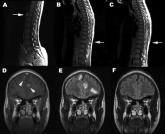

ArticleAcute paraplegia in a patient with AIDS and a normal CSF examinationAuthor:T. AldeenPublish date: June 20, 2008Read More